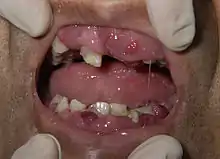

Syndrome tumoral

Le syndrome tumoral est lié à la dissémination des blastes hors de la moelle osseuses et de la accumulation dans les organes. Il peut se traduire cliniquement par[31] :

- une augmentation de volume de certains organes : splénomégalie, hépatomégalie ;

- des douleurs articulaires ;

- une atteinte cutanée (sudation nocturne) ;

- une atteinte muqueuse avec notamment une hypertrophie gingivale (augmentation du volume des gencives) ;

- une atteinte neuroméningée lors de l'envahissement du système nerveux central, pouvant être accompagnée de signes neurologiques.